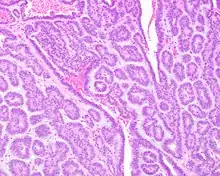

Canalicular adenoma is a type of growth that occurs in human salivary glands. It is a benign growth which occurs in the epithelial cells, and is typically arranged in columns of cells that form interconnecting cords. Canalicular adenoma is a very rare benign neoplasm; it constitutes about 1% of all salivary gland tumors and about 4% of all benign salivary gland tumors.[1][2]

Canalicular adenoma growths are usually small at the time they are noticed, with an average size of about 1.6 cm.[1] Their histologic appearance is very distinct, with a channel-like pattern between cords and ribbons; the pattern has been described as resembling a "string of pearls."

The growths often contain are often small bight squamous balls, or morules. They also tyipcally contain a well-developed supporting tissue - a fibrous stroma - which is rich in hyaluronic acid and chondroitin sulphate.[1] In a few cases, the growths may contain small calcium deposits or microliths. Although it is seldom necessary, a pathologist can confirm the existence of canalicular adenoma through immunohistochemistry studies, with the cells reacting with pancytokeratin, S100 protein and SOX10, with a delicate GFAP reaction around the periphery.[5][1][6][7] Although it is a benign tumor, a positive diagnosis of canalicular adenoma may be necessary to exclude the existence of other medical conditions such as a basal cell adenoma, pleomorphic adenoma, adenoid cystic carcinoma, and polymorphous adenocarcinoma.